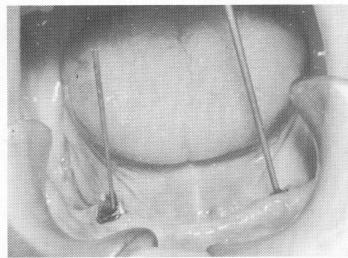

The two bicuspid teeth were prepared to their cementoenamel junctions, and endodontic stabilizers were used as additional support (Fig. 13-40). A

Three pin type implants were drilled through predetermined holes in the anterior part of the

Fig. 13-40. Two remaining strategically situated roots were further supported with endodontic stabilizers.